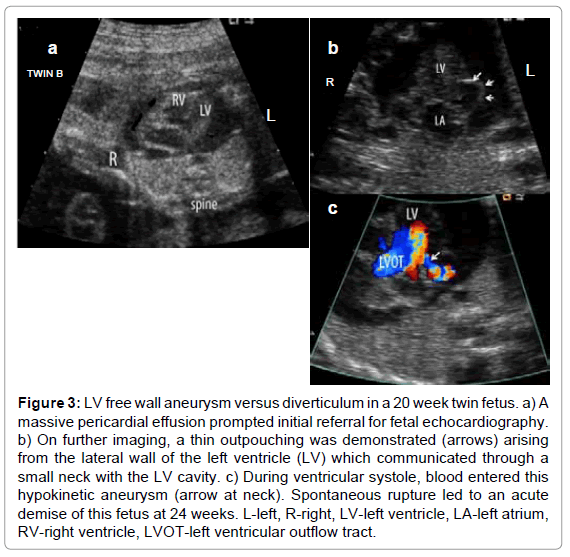

To date, most forms of congenital structural heart disease have been successfully diagnosed in utero, and the details of the cardiovascular anatomy defined including evaluation of systemic and pulmonary venous connections (Figure 1) and aortic and ductal arch position relative to the trachea, are often quite comparable to that of postnatal exams [11-13]. However, the unique parallel circulation of the fetus with right and left ventricles that have comparable filling pressures and afterload, the presence of fetal shunts, and the lack of clinical information beyond noninvasive imaging provides unique challenges to defining lesion severity. For instance, retrograde ductus arteriosus flow in lesions with pulmonary stenosis heralds critical obstruction [14]; however, in its absence, the severity of pulmonary outflow obstruction is often grossly inferred by the size and growth of the main pulmonary artery and its size relative to the aorta [15,16]. Even then, monitoring of systemic oxygen saturations after delivery until ductal closure is still the standard of care. Subtle discrepancies in ventricular, great artery and, most consistently, arch size may be the only abnormalities identified that lead to a suspected diagnosis of discrete juxtaductal coarctation of the aorta which clinically manifests postnatally only after the ductus arteriosus begins to constrict (Figure 2) [17,18]. Occasionally in more severe coarctation, however, distal arch hypoplasia and a posterior shelf may be identified, but even then, determining whether the lesion will warrant neonatal surgical intervention may not be possible until after ductal constriction in the neonatal period [19]. Finally, differences in ventricular preload before and after birth result in an inability to consistently determine whether or not a fetal left or right ventricle that appears borderline in dimension will be sufficient to sustain the systemic or pulmonary circulation after birth. Thus our prenatal counseling must take into consideration such limitations. Our postnatal management, as well, cannot be fully guided by prenatal findings. A small fetal left heart associated with coarctation of the aorta, for instance, may have more potential to dilate with augmented preload over the first several days after birth than what might have been predicted based on prenatal features (unpublished observations). Better delineation of structural and functional features of a borderline ventricle that will not be sufficient to sustain the systemic or pulmonary circulation after birth is critical for improved prenatal counseling and postnatal management. Certainly, this is also an area within which we struggle in the management of patients postnatally.

clinical-experimental-cardiology-atrial-isomerism

Figure 1: Images from a 30 week fetus with left atrial isomerism, mesocardia and anomalous systemic and pulmonary venous connections. Left and right pulmonary veins (a & b, arrows) and left and right hepatic veins (c & d, arrows) can be seen connecting on either side of the atrial septum by 2D and color flow map imaging. A coronary sinoseptal defect was identified (*). The dilated azygous vein connected with a left superior vena cava that drained into the left sided atrium. Surgical repair with intra-atrial baffling of systemic and pulmonary veins was used to correct this lesion at 9 months. L-left, R-right, Lt-left, Rt-right, DAo-descending aorta, RV-right ventricle, LV-left ventricle, PV-pulmonary vein, LSVC-left superior vena cava.